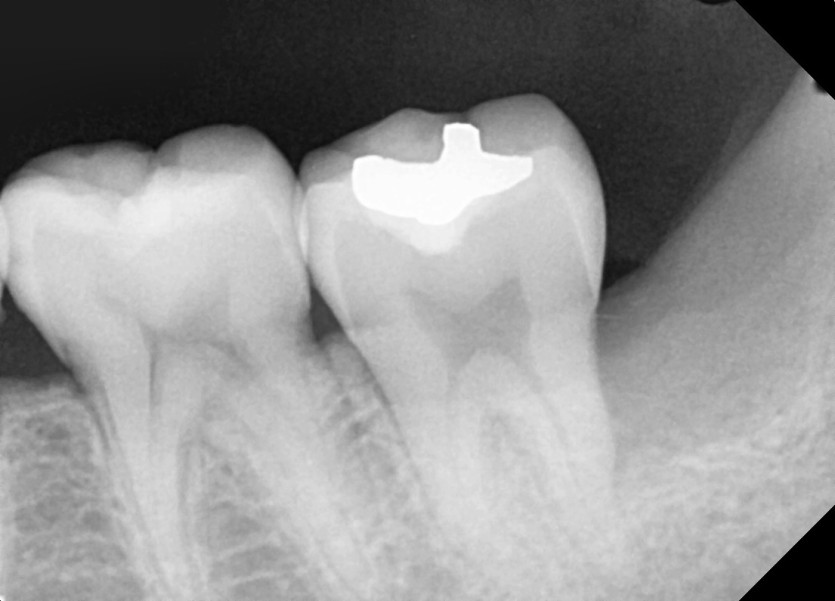

#38,48 사랑니 발치

구강 외과 전문의가 당일 발치했습니다.